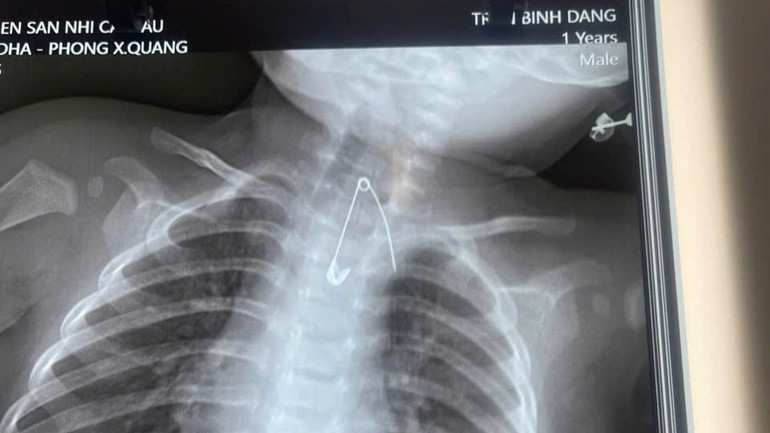

Hình ảnh từ thiết bị chuyên dụng tại Bệnh viện Sản-Nhi Cà Mau thể hiện dị vật là kim tây trong cơ thể trẻ 7 tháng tuổi. (Ảnh do bệnh viện cung cấp)

Kết quả chẩn đoán hình ảnh cho thấy một chiếc kim tây dài khoảng 3cm nằm sâu trong mô mềm, ở vị trí cực kỳ nguy hiểm là sát động mạch chủ.

Các bác sĩ cảnh báo, dị vật này chỉ cần dịch chuyển nhỏ cũng có thể gây thủng mạch máu lớn, dẫn đến xuất huyết ồ ạt không thể cứu chữa. Rất may mắn, ê-kíp phẫu thuật đã can thiệp kịp thời, lấy dị vật ra an toàn.